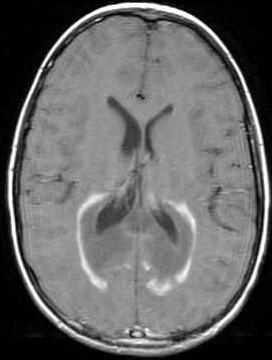

• Confluent, symmetric deep WM w/ Confluent, symmetric deep WM w/ leading edge enhancement leading edge enhancement

• Posterior in 80% Posterior in 80%

• Pons and medulla Pons and medulla

JA Phelan and LH Lowe, Univ. of Missouri - KC